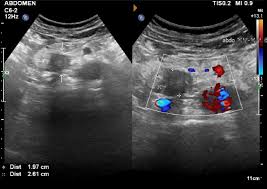

심장 초음파로 알 수 있는 병 ⑦ 심장 종양·혈전

드물지만 심장 안에 종양이나 혈전이 생기는 경우도 있습니다. 심장 초음파는 이러한 구조적 이상을 직접 눈으로 확인할 수 있어, 뇌졸중 위험 평가에도 활용됩니다. 이 또한 중요한 심장 초음파로 알 수 있는 병입니다.